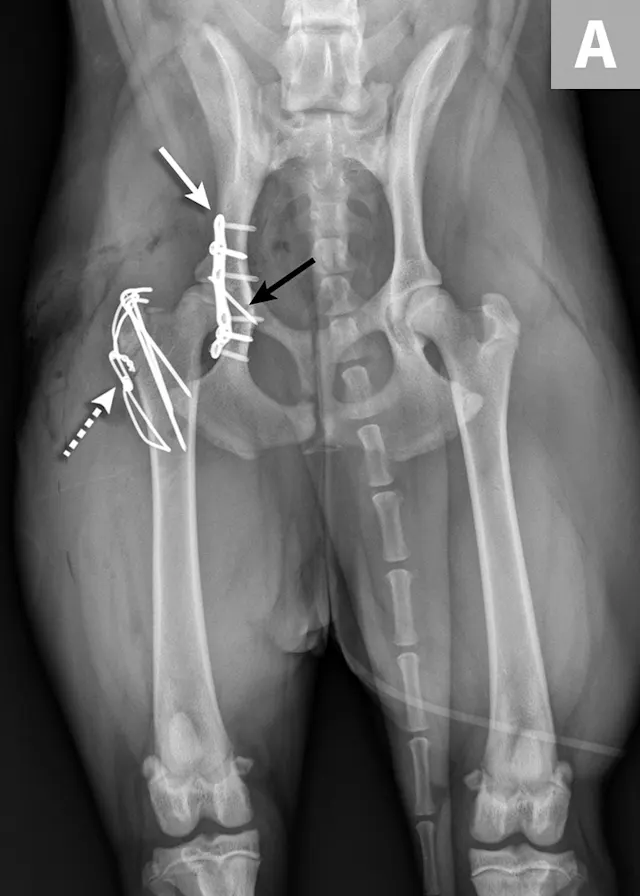

FIGURE 4A

Postoperative ventrodorsal (A) and lateral (B) projection images of the same dog in Figure 2. Fracture reduction was achieved with cross pins and a figure-eight hemicerclage wire (black arrows). Reduction was protected via application of a locking string-of-pearls neutralization plate (solid white arrows). To gain access to the full extent of the fracture, a greater trochanteric osteotomy was performed and stabilized with a positional screw and pin (dashed arrows). The ventrodorsal postoperative radiograph revealed a sacral fracture not previously appreciated (arrowhead). The fracture was successfully treated with conservative management.